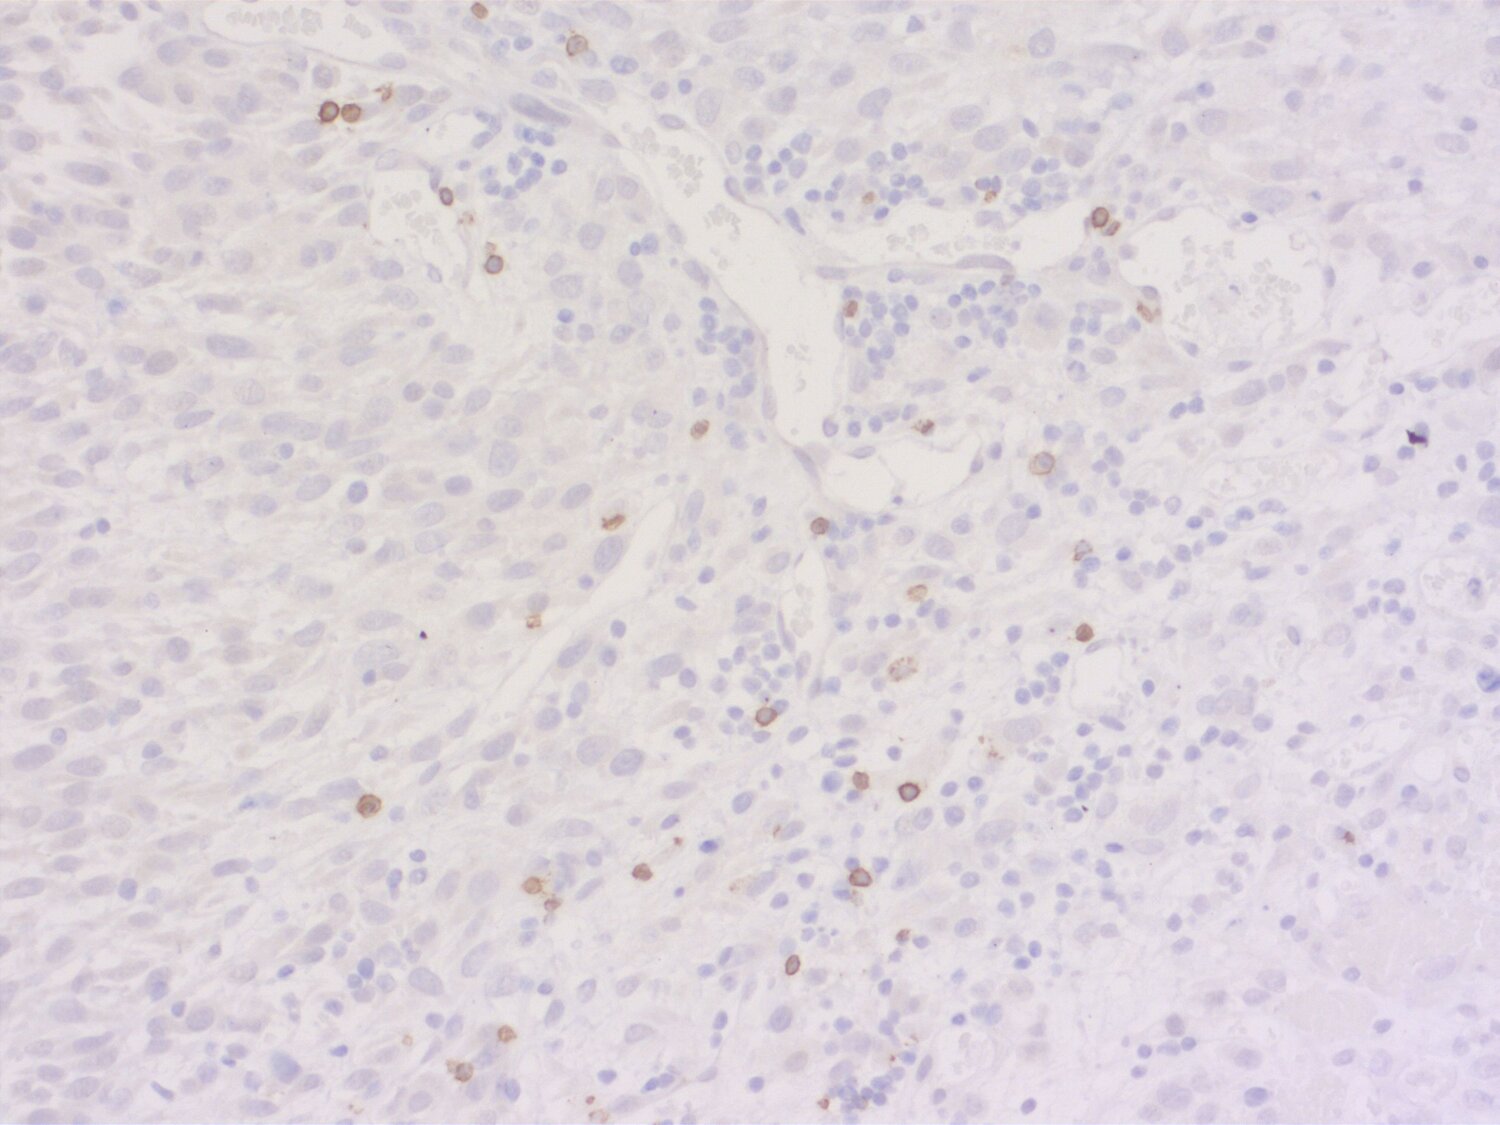

Indirect immunostaining of a formalin fixed paraffin-embedded mouse breast cancer model with rabbit anti-mouse CD19 (cat. no.: HS-439 003; DAB). Nuclei have been visualized by haematoxylin staining (blue).